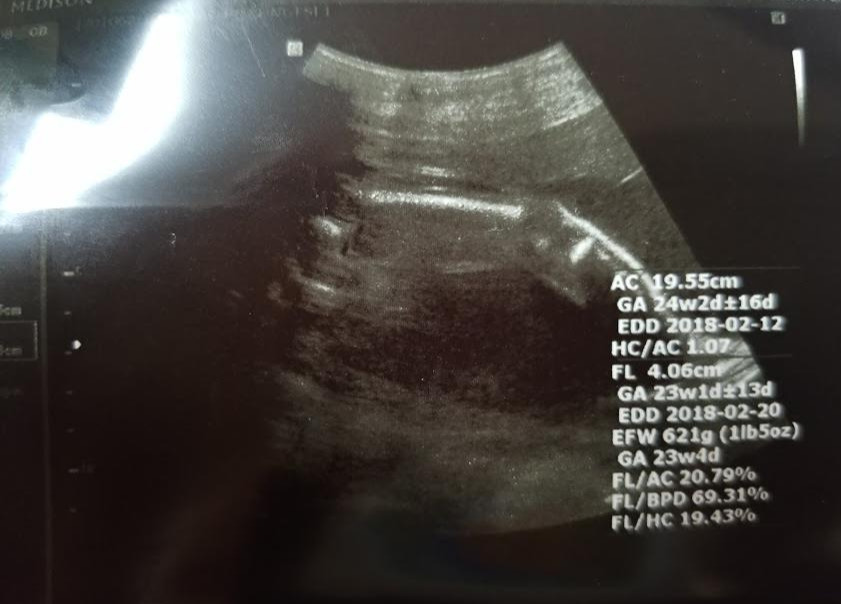

오늘 정기검진을 가보니 아기가 또 많이 자라 있다. 체중은 621그램 정도. 머리둘레, 배 둘레, 허벅지 길이 등이 다 주수보다 크다. 배 둘레는 주수보다 열흘 정도 앞서있다.

초음파 탐촉자로 다리 한쪽의 단면을 보여주었는데, 허벅지와 종아리의 구분이 명확하고 실루엣이 꼭 근육질의 다리 같았다.